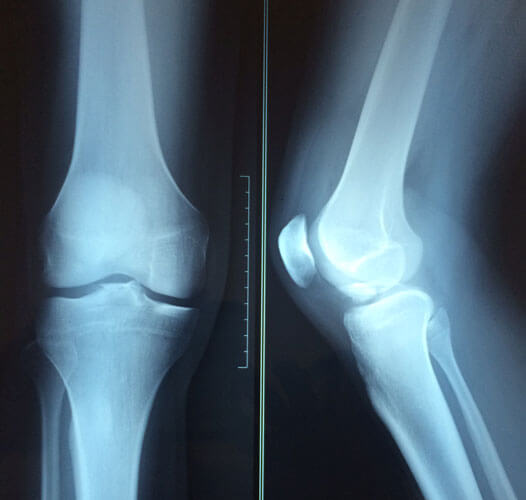

Arthroscopy Surgery